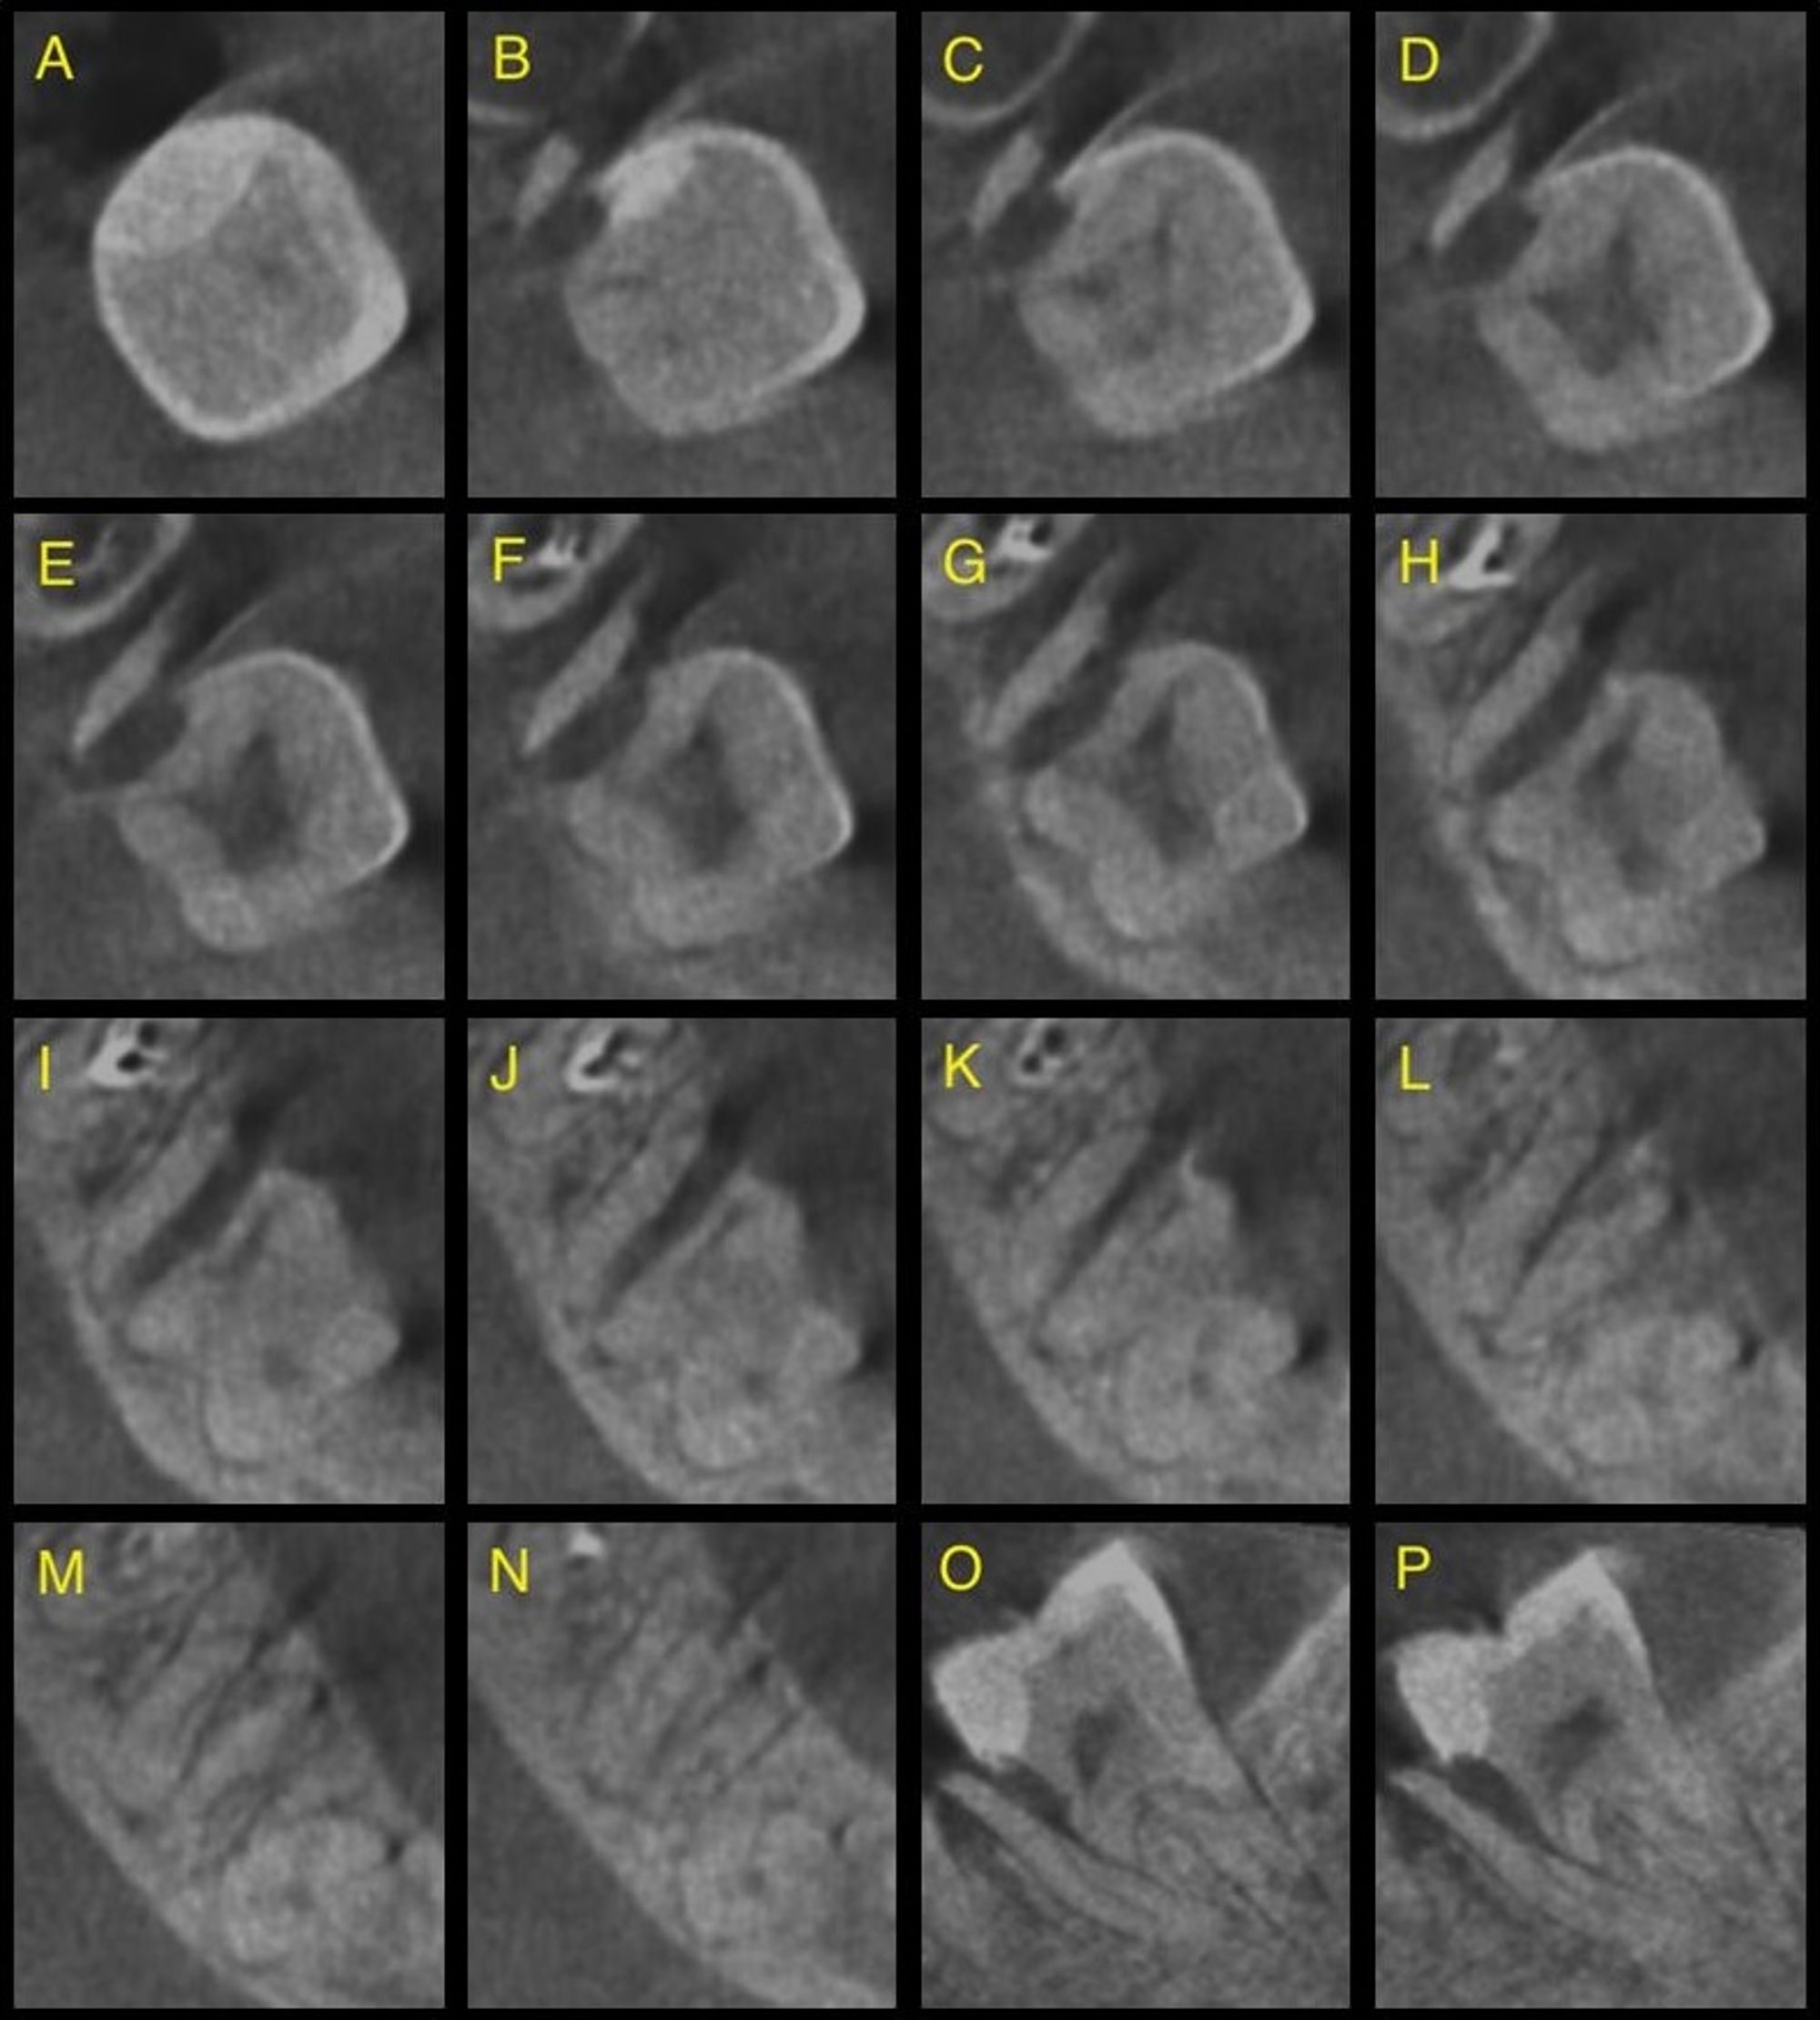

An oblique crown-root fracture was detected incidentally in the cervical middle third of the mesial root of a non-endodontically treated second lower right molar. Because the tooth was asymptomatic, the pulp responded positively to testing and no periapical pathosis was detected, an endodontic treatment was not indicated. Considering the unusual condition of tooth 47, substantial efforts were made to save tooth 46, which had been extensively destroyed by caries. A control cone beam computed tomography (CBCT) acquired 12 months after completion of the endodontic treatment of tooth 46 revealed almost complete resolution of the periapical pathosis in the first right molar, no changes in the fracture line and no periradicular radiolucency in the second right molar. The loss of this tooth could have resulted in postextraction atrophy of the alveolar bone and loss of support for the fractured root of the adjacent tooth.